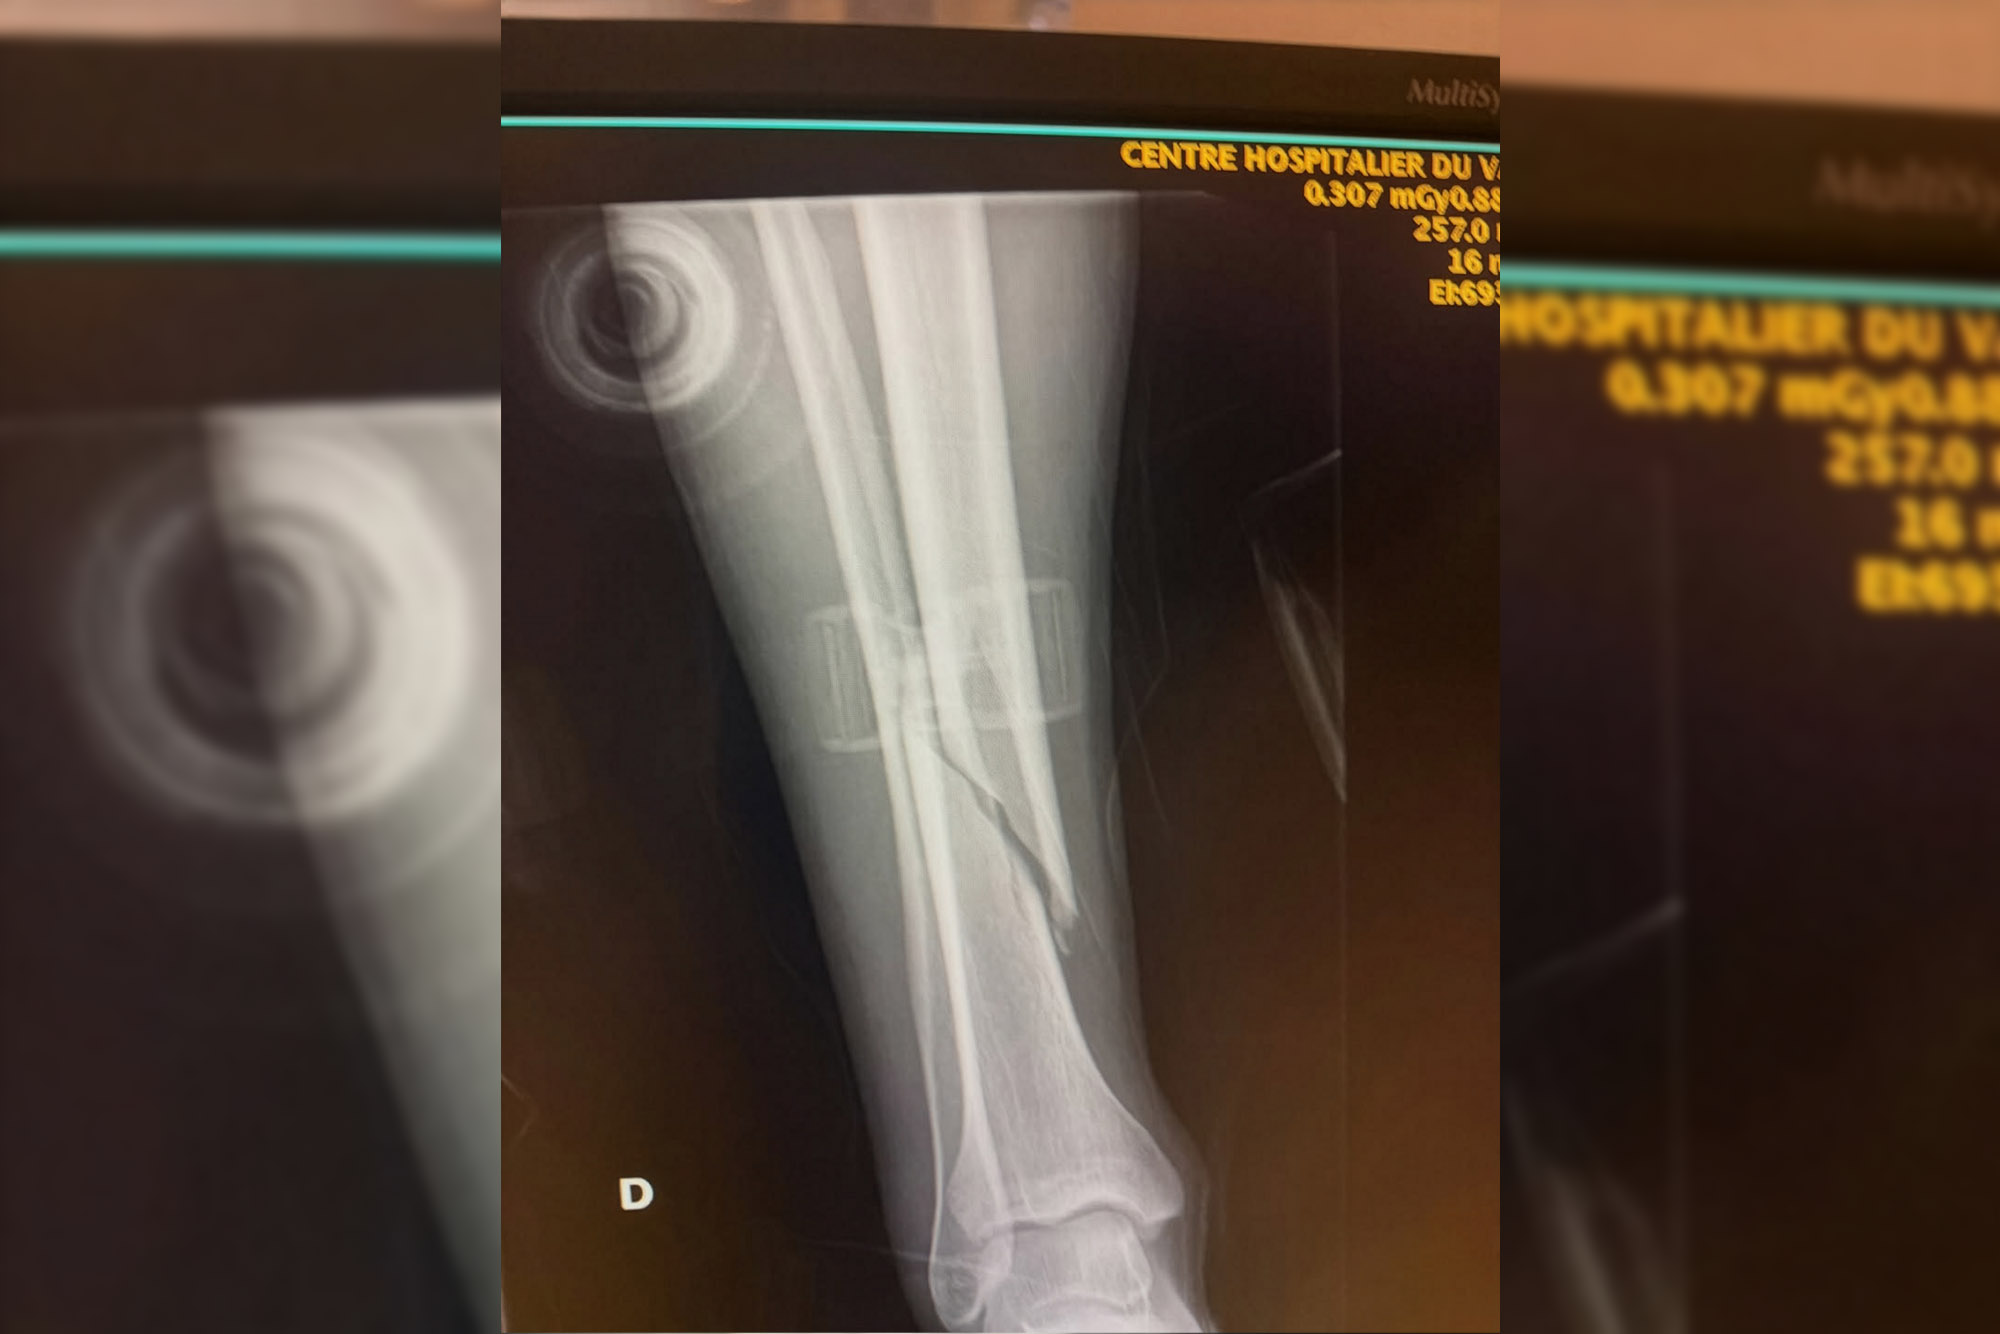

Ирландский гонщик пропустит начала сезона на Кубке Мира из-за перелома большеберцовой кости на правой ноге.

На своей страничке Ронан написал, что к перелому привел неудачный «топ» ногой по земле в повороте. Сам момент, привёдший к перелому, можно посмотреть в карусели, он третий с конца.